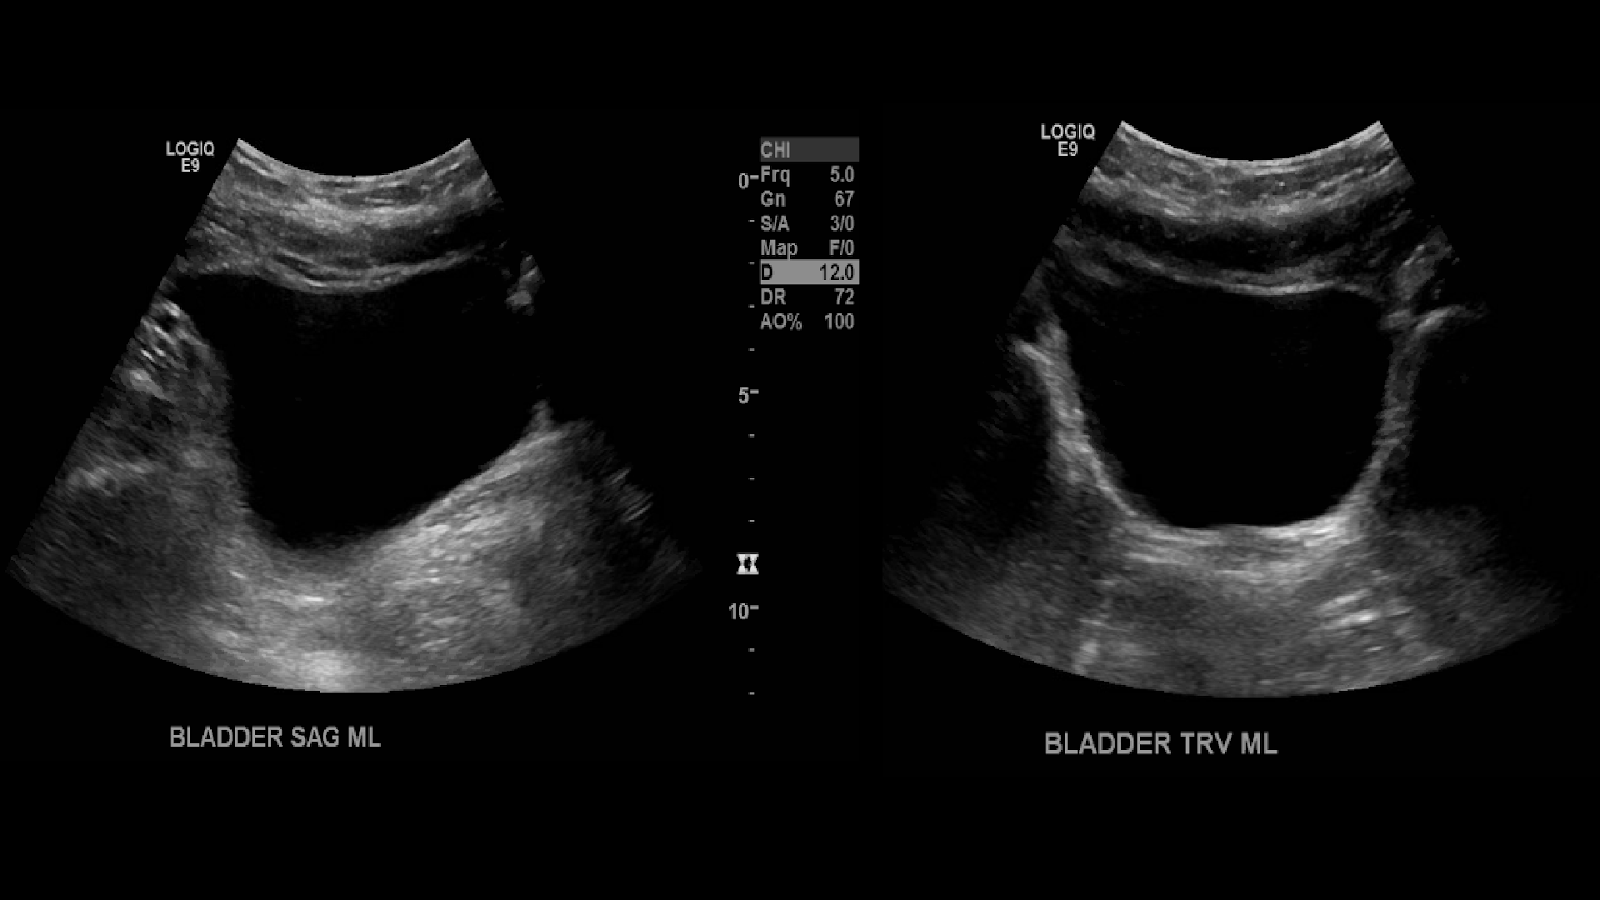

I then move on to image the bladder in sagittal and transverse.